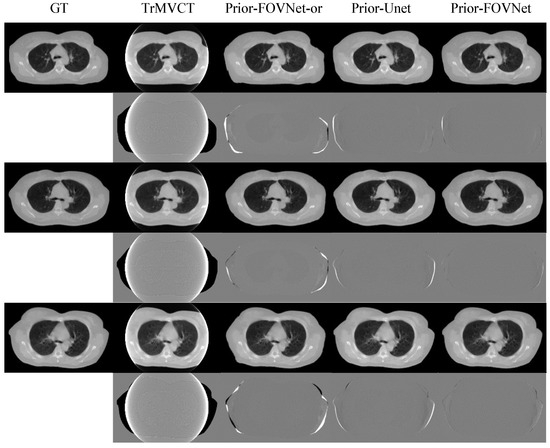

4.3. Results of Clinical Patient Data